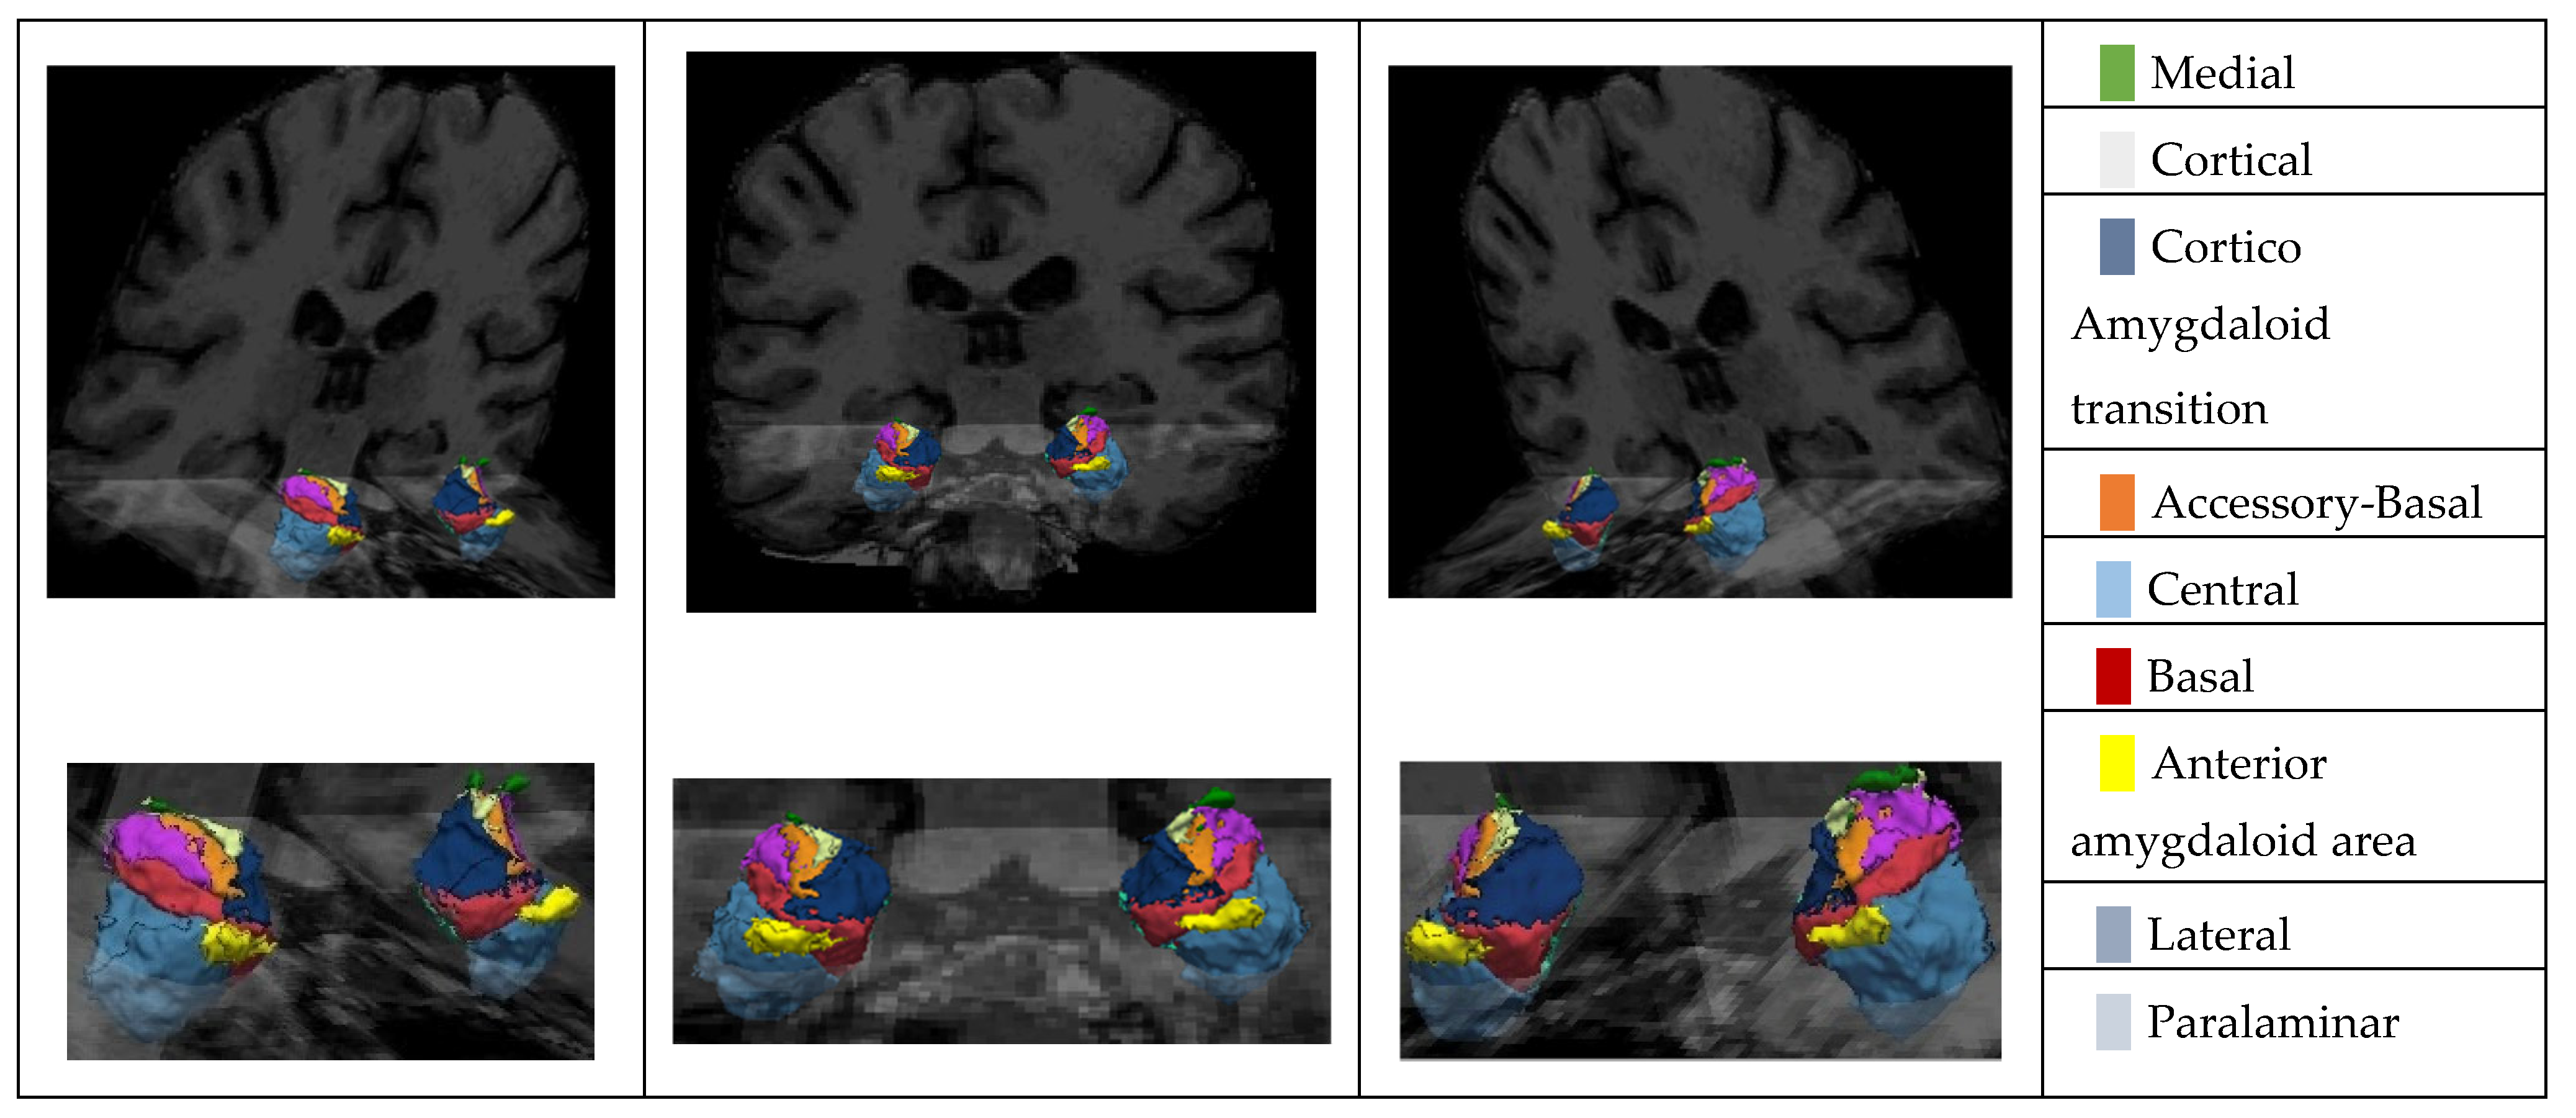

We used an automatic atlas created by an atlas-building algorithm based on Bayesian inference. This atlas, integrated into FreeSurfer, can automatically segment nine amygdala nuclei from a standard-resolution structural magnetic resonance image (see Figure 2). The atlas is publicly available in two datasets: ADNI and ABIDE. ADNI is documented and can be available for download online (https://adni.loni.usc.edu/data-samples/adni-data/ accessed on 1 September 2024).

Figure 2. T1 MRI fusion with the 3D reconstruction of the Amygdala Nuclei.